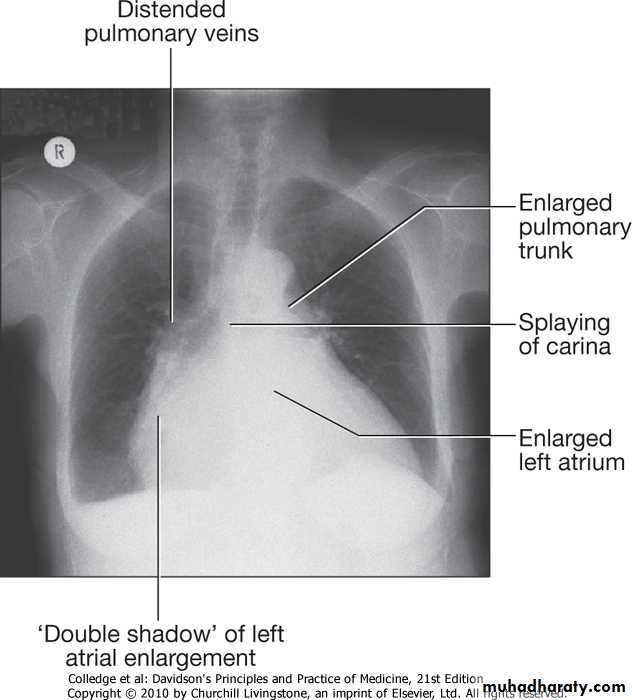

• CXR (CARDIOMEGALY ,PULM.EDEMA)